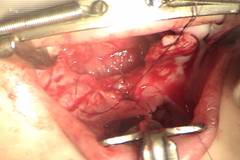

5. Lo importante es crear una hamaca de músculo que mantiene traccionado hacia atrás ese velo del paladar (Fig. 8 y 9). Disecar los músculos para reorientarlos no ha probado ser beneficioso ( ), en cambio ese disección si produce mas cicatriz dentro del paladar mismo y hace que si se quiere hacer un Furlow en un segundo tiempo sea mas difícil y con menos posibilidades de éxito. Hay que tener en cuenta que las posibilidades de que un paciente con una hendidura amplia desarrolle una incompetencia velo faríngea son mucho mas altas que las de un paciente con una hendidura estrecha.

Figuras 8 y 9: Sutura en la línea media de las diferentes estructuras sin disecar el músculo de las mucosas, nótese como al crear una hamaca con la sutura de los músculos el alargamiento se mantiene.